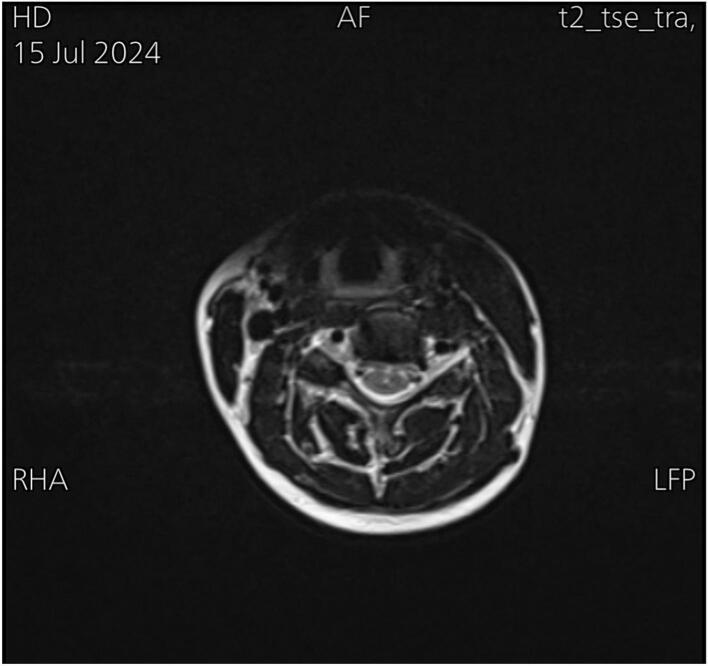

A 20-year-old woman presented with restricted neck mobility and facial asymmetry. Clinical examination and imaging confirmed unilateral sternocleidomastoid muscle (SCM) contracture with an absent clavicular head. The patient underwent unilateral sternocleidomastoid muscle (SCM) resection. Postoperative rehabilitation significantly improved mobility and aesthetic concerns.

一名20岁女性出现颈部活动受限和面部不对称。临床检查和影像学检查证实单侧胸锁乳突肌(SCM)挛缩且锁骨头部缺如。患者接受了单侧胸锁乳突肌(SCM)切除术。术后康复显著改善了活动能力并缓解了美观问题。